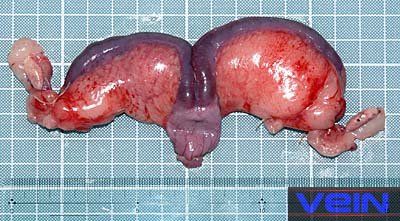

La pyometra est souvent causée par Pasteurella multocida,

qui entraîne la formation d’abcès dans les ovaires. L’utérus est dilaté et

généralement rempli de pus. Les infections aiguës sont souvent accompagnées